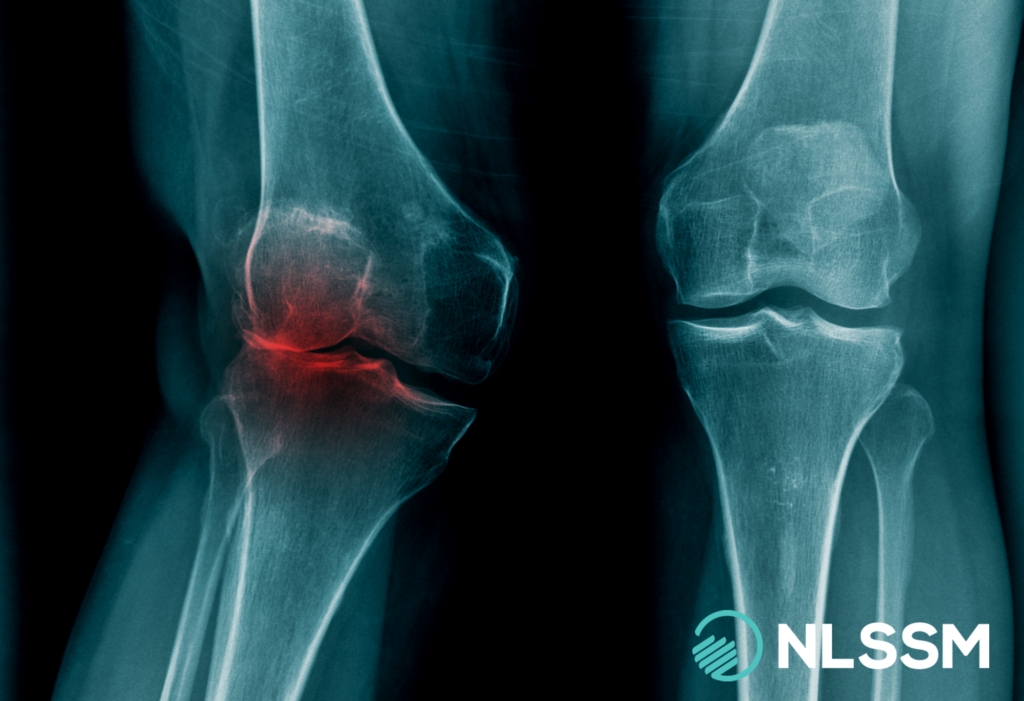

What is Patella Femoral Pain Syndrome?

Patellofemoral pain syndrome (PFPS), often called “runner’s knee” or anterior knee pain, is a common condition. The differential diagnosis of PSFS includes chondromalacia and patellar tendonopathy. Chondromalacia patella is not classified within the broader category of PFPS, as its underlying pathophysiology differs and requires a distinct treatment approach.[1]

The patella is the largest sesamoid bone in the body, embedded within the tendon of the quadriceps muscle group. It sits in the trochlear groove of the femur and acts as a pulley system for the knee. Superiorly, it is attached to the quadriceps tendon, which connects the four quadriceps muscles to the patella. Inferiorly, it continues as the patellar tendon (or ligament), attaching to the tibial tuberosity.

Functionally, the patella increases the mechanical advantage of the quadriceps by improving the angle of pull, enhancing knee extension strength and efficiency. It also helps distribute compressive forces across the patellofemoral joint during activities such as squatting, running, and stair climbing.